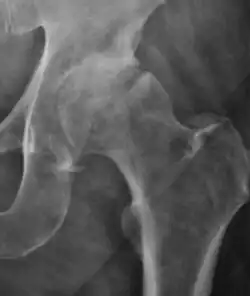

Plain radiography allows us to categorize the hip as normal or dysplastic or with impingement signs (pincer, cam, or a combination of both). Besides these, pathologic processes like osteoarthritis, inflammatory diseases, infection, or tumors can also be identified (Figure 1).[1]

Figure 1.

-

Radiography in normal hip -

X-ray in pincer impingement type of hip dysplasia -

X-ray of cam -

Hip in osteoarthritis -

Septic arthritis

X-ray in pediatrics

There are other pathological conditions that can affect the hip joint and radiographs help to make the appropriate diagnosis. Acute bacterial septic arthritis can be diagnosed by radiographs when a fast regional osteoporosis and destructive monoarticular process develops (Figure 1(f)). In case of tuberculous or brucella arthritis it is manifested as a slow progressive process, and diagnosis may be delayed.[1]

Synovial chondromatosis can be confidently diagnosed by X-ray when calcified cartilaginous chondromas are seen. However, other synovial proliferative processes, such as pigmented villonodular synovitis, require MRI for accurate diagnosis, although noncalcified synovitis can be suspected in radiographs by indirect signs, such as soft tissue swelling and/or erosions in the femoral head, femoral neck, or acetabulum (Figure 7).[1]